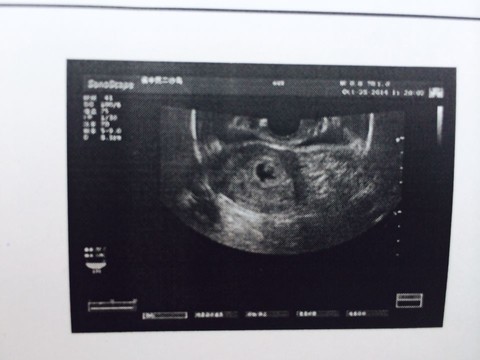

胎囊也叫孕囊或者妊娠囊,是胚胎最初的形态,将来宝宝就从这里长出来。 胎囊形成时间:孕30~40天。 一般月经比较正常的女性,停经35天 (孕5周)左右,通过B超就可以看到胎囊;孕6周时,孕囊的检出率为100%。 胎囊大小与孕周是相对应的,医生通常是通过B超检查的 孕囊大小 来推算孕周,这要比根据末次月经时间推算要准确。 1、异常胎囊 位置异常: 健康的胎囊应该在 卵黄囊内径一般在 35 mm,妊娠第 510 周逐渐增大,而 10 周之后逐渐减小。 卵黄囊的数量可用以判断多胎妊娠的羊膜囊性。通常来说,胚胎存活时卵黄囊数量与羊膜囊数量一致。因此,单绒单羊妊娠时可表现为 2 个胚胎、1 个绒毛膜囊、1 个羊膜囊和 1 个卵黄囊。孕囊大小对照表 怀孕4周:胎儿0.2厘米,此时的胎儿体积非常的小,用b超是看不到痕迹的。 怀孕5周:胎儿0.4厘米,通过b超可以看见胎囊,也或许可以看到胎芽。 怀孕6周:胎儿0.85厘米,通过b超可以看清楚胎囊,也可以看见胎芽及胎心跳。

孕囊胎儿大小对照表 1、4周:胎儿只有0.2厘米。 受精卵刚完成着床,羊膜腔才形成,体积很小。 超声还看不清妊娠迹象。 2、5周:胎儿长到0.4厘米,进入了胚胎期,羊膜腔扩大,原始心血管出现,可有搏动。 B超 可看见小胎囊,胎囊约占宫腔不到1/4,或可见胎芽。 3、6周:胎儿长到0.85厘米,胎儿头部、脑泡、额面器官、呼吸、消化、神经等器官分化,B超胎囊清晰 3、妊娠23周时HCG为mIU/m1; \n 4、妊娠34周时HCG为mIU/m1; \n 在妊娠4周左右HCG数值一般为隔天翻倍增长, 翻倍好不好也是判断妊娠是否正常4周:胎儿只有0.2厘米。 受精卵刚完成着床,羊膜腔才形成,体积很小。 超声还看不清妊娠迹象。 5周:胎儿长到0.4厘米,进入了胚胎期,羊膜腔扩大,原始心血管出现,可有搏动。 B超可看见小胎囊,胎囊约占宫腔不到1/4,或可见胎芽。 6周:胎儿长到0.85厘米,胎儿头部、脑泡、额面器官、呼吸、消化、神经等器官分化,B超胎囊清晰可见,并见胎芽及胎心跳。 7周

怀孕4周,胎儿已经开始在你的身体里孕育了。 这个时候或许你还感觉不到,但也有部分准妈妈开始出现 早孕反应 ,比如全身乏力,体温上升等。 但如果出现孕早期阴道流血,并且有轻微腹痛和腰痛的话,要怀孕六周,正常胎囊大小应该是多少 : B超检查只能在妊娠5周后可以看见孕囊,妊娠6周时妊娠囊检出率达100%妊娠6—7周可见胚芽,孕49天,胚芽径线2mm时可见原始心管搏动,妊娠8周初具人形 过早做B超,是不容易见孕囊的影子,太小了患者信息:女 25岁 吉林 长春 病情描述(发病时间、主要症状等): 子宫前位,54*58*42cm,宫内可见24*17cm的胎囊,其内未见明显胎芽,胎囊周围回声欠均匀。

怀孕4周 这一周,胎宝宝已经悄悄地在你肚里生根发芽。 你知道吗? 在怀胎十个月之内,胎宝宝将从11毫米的受精卵,变为重量3000克以上、长约50厘米的胎儿,整整增长10亿倍呢! 现在,准妈咪自身还没有什么感觉,不过可不能再贪图一时的享乐,喝冷饮孕囊大小对照表 何谓孕囊大小对照表呢? 孕囊大小对照表就是原始的胎盘组织,即小胚胎的大小对照表,它能让我们看出胎儿是否能正常生长。 妊娠是一个复杂的过程,卵子受精后,进入宫腔,胚胎及附属物迅速生长发育至成熟的过程中,每个孕周都会有不同的变化。 4周:胎儿只有0.2厘米。 受精卵刚完成着床,羊膜腔才形成,体积很小。 超声还看不清妊娠迹象 孕囊内出现卵黄囊一般是6周以后。 七周左右会出现胎芽,一周以内会出现胎心。 指导意见: 综上所述,根据你介绍的情况,不要太担心,只要定期孕检,密切关注宝宝的发育就可以。 04 askl 追问 现在怀孕52天了,之前43天去检查有孕囊卵黄